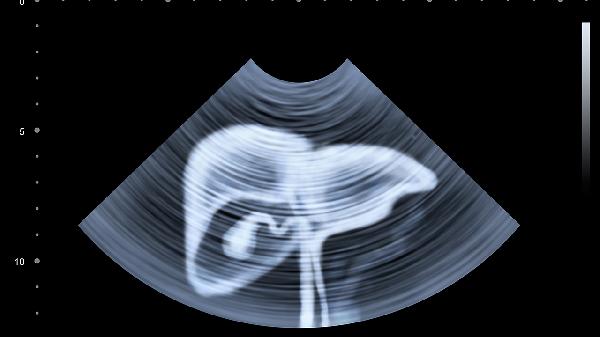

腸易激綜合征、炎癥性腸病等可能伴隨腹脹腹痛,需通過腸鏡等檢查確診。治療需針對(duì)原發(fā)病,如美沙拉嗪用于潰瘍性結(jié)腸炎,匹維溴銨緩解腸痙攣。